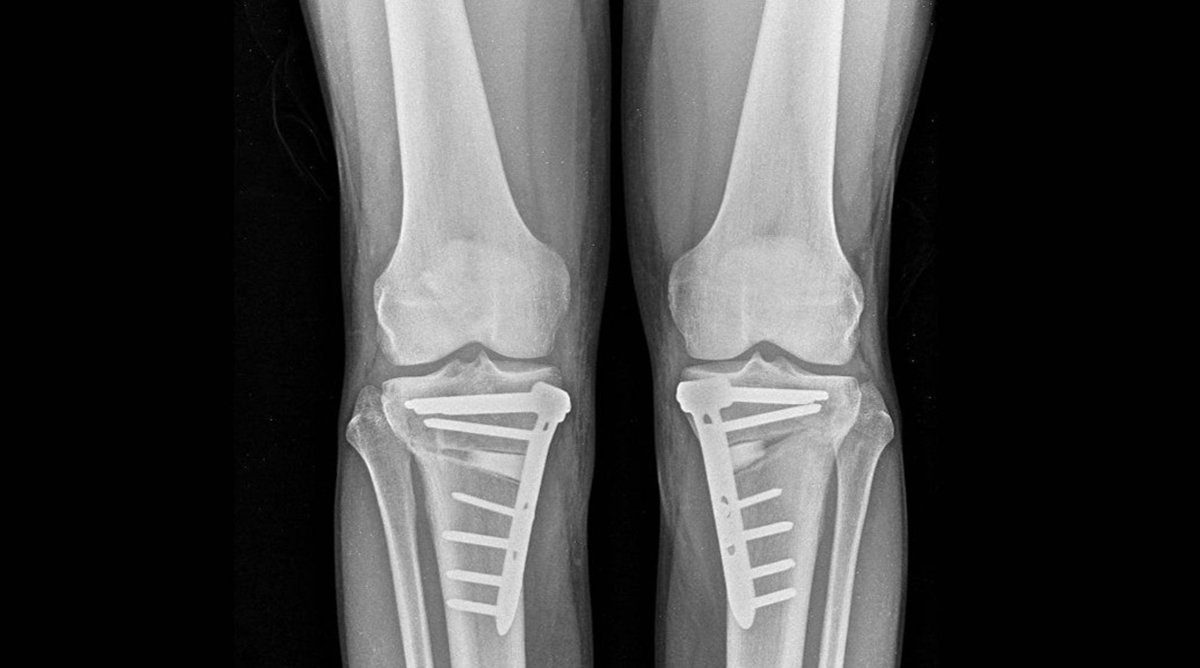

Radiografías de rodilla.

Radiografías de rodilla. - SOCIALNIUS

Esta técnica quirúrgica corrige las deformidades de las piernas, como el 'genu varo', una deformidad que provoca que las rodillas se curven hacia fuera, y el 'genu valgo', que genera piernas en forma de 'X'; preserva la rodilla natural y ayuda a frenar la artrosis sin necesidad de implantar una prótesis.

La osteotomía consiste en realizar un corte planificado en el hueso (tibia o fémur) para modificar el eje de carga de la pierna. De esta forma, se redistribuyen las fuerzas sobre la articulación, aliviando el dolor y deteniendo la progresión del desgaste.

A este respecto, el especialista ha comentado que el "gran cambio" no es la técnica, conocida, sino la "enorme mejora" que ha experimentado gracias a avances tecnológicos como la planificación digital tridimensional y los nuevos sistemas de fijación e implantes. "Hoy podemos planificar en el ordenador la corrección exacta y, si lo deseamos, imprimir en 3D guías quirúrgicas personalizadas. Además, los nuevos sistemas de fijación permiten que el paciente empiece a apoyar la pierna a las 24 horas", ha detallado Arnal.